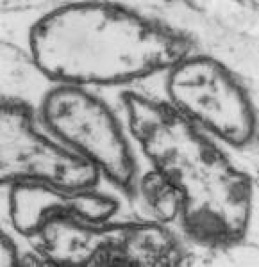

The following electron micrographs demonstrate the effect of Potentiated antimicrobials, against a multi-drug resistant Pseudomonas aeruginosa.

Normal “Intact” cell Membrane Before Treatment

Potentiator   induced Cytoplasmic Leakage Facilitating Bacteria Death